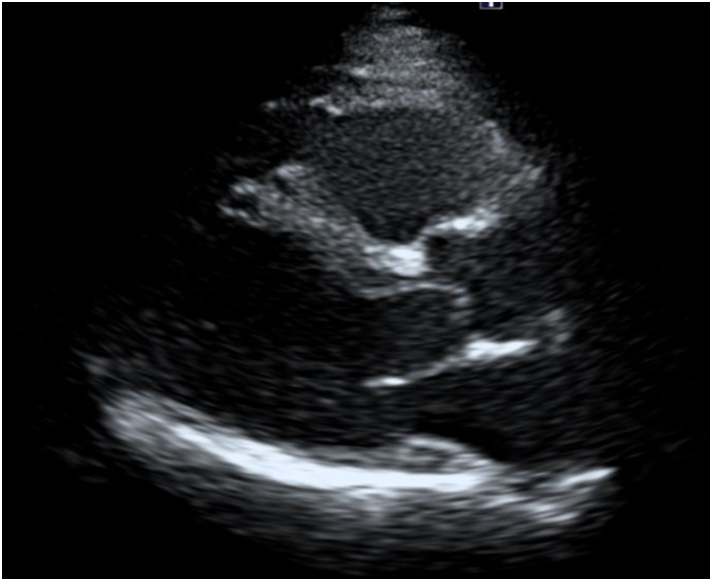

2. 심장초음파

• 심장초음파 검사 결과: 정상 심장초음파 검사 결과: 정상